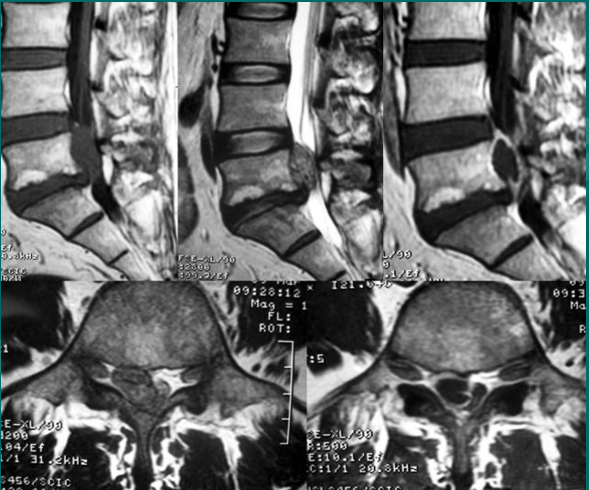

正常腰椎间盘表现

正常腰椎间盘后缘不超过椎体骨性终板的后缘,且中部略有凹陷呈肾形。

一个健康的45岁男性的L4椎间盘的轴状面观。

髓核区及周围的纤椎环区。

靠近L5神经根的椎间盘后缘的凹度,这是正常健康椎间盘的象征。

L4发出神经根更靠侧方一点。这就不难理解为什么如果有大的椎间盘突出或椎管狭窄,发出神经根L4及过往神经根L5将同时受压。

在此图中,可清楚地看到悬挂在硬膜囊内的细小的神经根(L5神经根及S1神经根),它们以不完全有绪地状态排列着。注意,神经孔是很开阔的(浅黄色区),表明没有因邻近椎间关节问题形成在的椎管狭窄。T2加权象对于察看退化性椎间盘病是最好的,因为T2像将富含水份的结构表现为亮白色, 含水少的区域表现为黑色。

位于椎体之间的椎间盘应是白色的(含水多)。注意黑颜色(脱水的)的L5椎间盘(L5与骶骨之间的椎间盘),这代表了中度到重度的退化性椎间盘病。